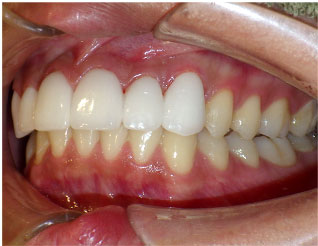

- ブリッジ 症例写真 B-0113FZC8本 女性モニターの方です。

この方は古い差し歯の黄ばみを治したいとご来院されました。 奥歯に欠損もありましたので、前歯はジルコニアセラミック、奥はジルコニアブリッジで治しました。 1回の治療で前歯も奥歯も同時進行で治療します。 1回目の治療時に仮歯を入れますので、すぐに見た目が気にならなくなります。 治療回数は5回でした。